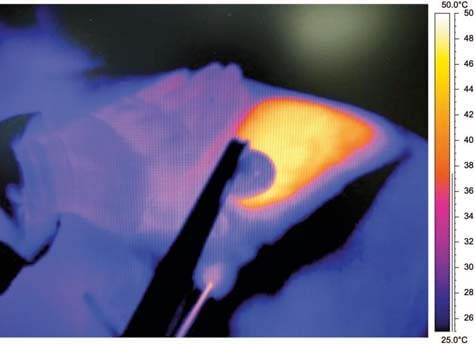

RFAL uses bipolar radiofrequency energy that has a controlled path. This makes the radio energy travel in a precise and efficient way that will increase patient safety and results of the procedure. The radio energy will heat up and tighten the skin at the same time as it destroys the fat deposits. Radio Frequency Lipo is the new medical sensation!